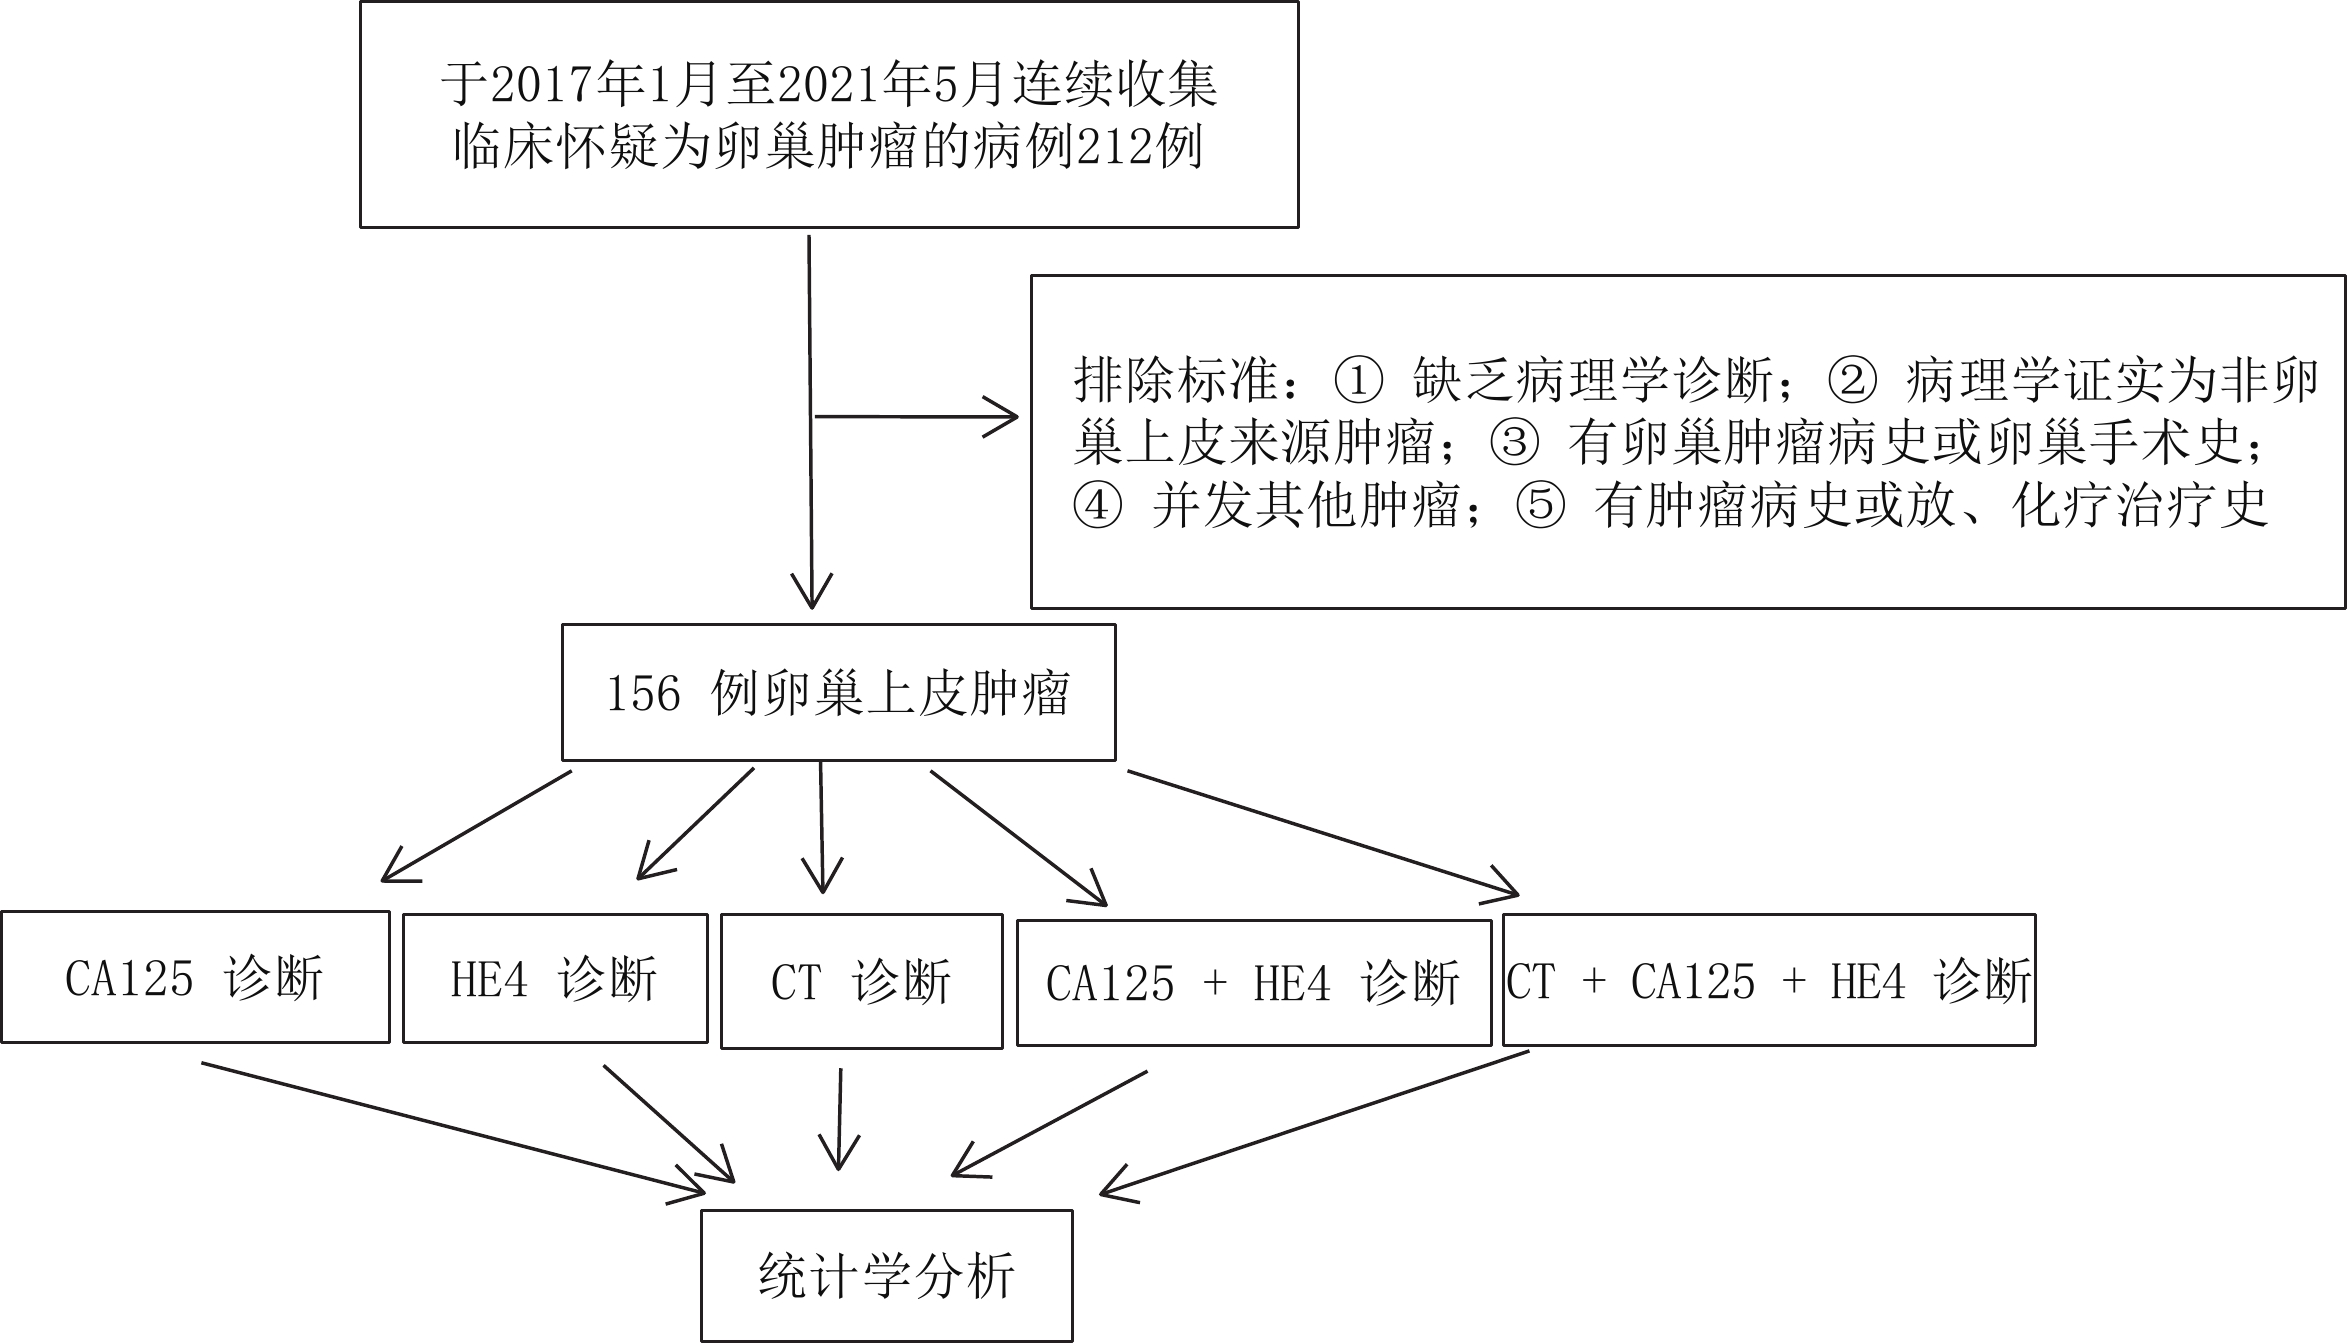

入选标准:卵巢原发上皮肿瘤首次确诊,既往无卵巢肿瘤病史及卵巢手术史;未并发其他肿瘤,无肿瘤病史或放、化疗等治疗史;术后经病理学确诊。按国际妇产科联盟(international federation of gynecology and obstetrics,FIGO)对卵巢上皮恶性肿瘤的分期[4],84例恶性肿瘤中Ⅰ期15例,Ⅱ期21例,Ⅲ 期37例,Ⅳ 期11例。其中浆液性囊腺癌61例、黏液性囊腺癌16例、子宫内膜样腺癌5例、透明细胞癌2例。156例病例为连续收集,入组路线图见图1。

表 1 血清CA125、HE4在卵巢上皮良、恶性肿瘤组中阳性率的比较Table 1. Comparison among positive rates of serum CA125 and HE4 in benign and malignant ovarian epithelial tumors分组 CA125 HE4 恶性肿瘤组(n=84) 85.71%(72/84) 80.95%(68/84) 良性肿瘤组(n=72) 38.89%(28/72) 22.22%(16/72) χ${} ^2$ 36.94 53.81 P 0.000 0.000 CT、血清CA125、HE4单独及联合应用对卵巢上皮恶性肿瘤的诊断结果比较显示CA125诊断的灵敏度高于HE4,HE4诊断特异度高于CA125,CA125联合HE4诊断的准确率高于CT;CT+CA125+HE4诊断准确率高于单独CT或肿瘤标志物诊断(表2),部分病例CT图像见图2~图5。